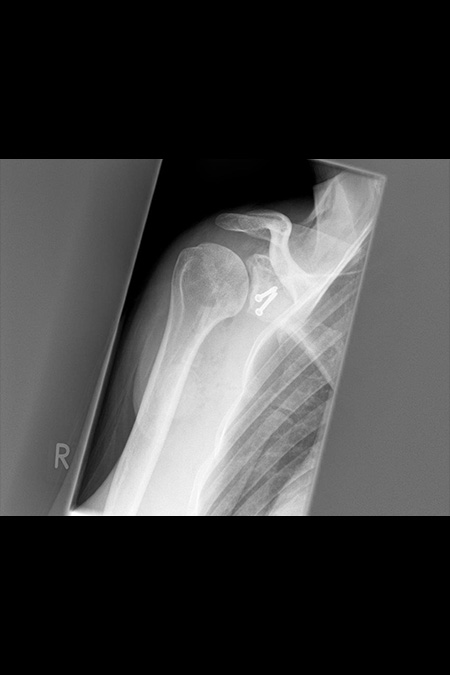

34 Jährige Patientin mit chronischer rechter Schulterinstabilität nach vorne unten. Bei der Analyse des Gelenkes fand sich in der 3D Schichtbilduntersuchung ein knöcherner Defekt (12% des Durchmessers) am vorderen unteren Pfannenrand. Operatives Vorgehen mit Spanaufbau des Defektes vom gleichseitigen Beckenkamm und Kapselstabilisation. Der Span wurde mit bioresorbierbaren Schrauben fixiert. Nach 3 Monaten bereits sehr gutes stabiles Bewegungsbild bei eingeheiltem Span. Noch Kraftaufbau erforderlich.

Knöcherner Defekt am unteren Pfannenrand

Knöcherner Defekt durch Span ausgeglichen